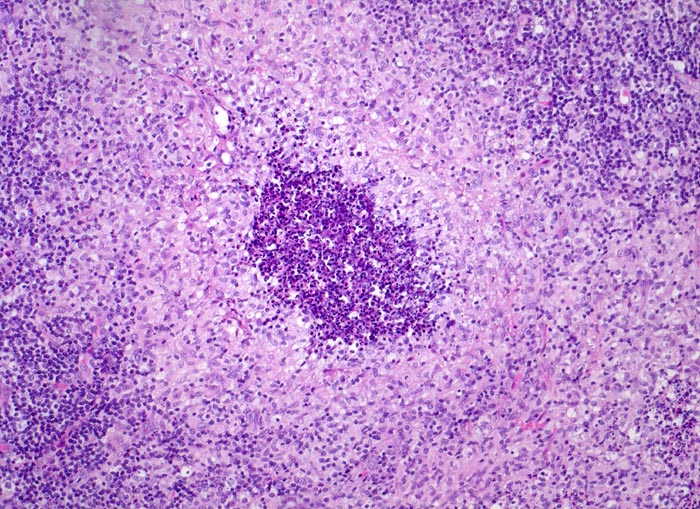

Morphologische Merkmale:

• Girlandenförmige basophile Nekrosezonen durchsetzt von neutrophilen Granulozyten (abszedierende Entzündung).

• Demarkierung der Abszesse durch palisadenförmig angeordnete epitheloide Histiozyten (heller Randwall um die Abszesse).

• Vereinzelt mehrkernige Riesenzellen im histiozytären Randwall.

• Vernarbte verdickte Lymphknotenkapsel.